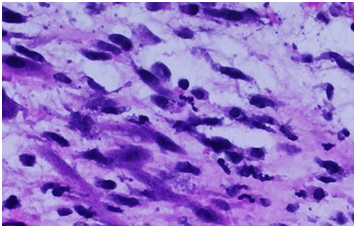

An 11-year-old girl with history of sickle cell trait and allergic rhinitis presented to the emergency department for pruritus. She had been evaluated at an urgent care clinic three weeks prior for generalized rash and pruritus, and was diagnosed with contact dermatitis. At current presentation, rash had resolved but she had persistent pruritus. No abdominal pain. She had scleral icterus, but family reported this was not uncommon as it occurred for over a year and seemed to get worse with her “seasonal allergies”. Initial assessment showed a thin nontoxic appearing girl with normal vital signs and an exam significant for icteric sclerae, excoriations but no rash, and a nontender abdomen with liver palpable 2cm below the right costal margin. Laboratory results showed elevations in direct bilirubin, alkaline phosphatase, and GGT. Ultrasound showed intrahepatic biliary dilation with an echogenic area in the common hepatic duct suggestive of sludge. She had a magnetic resonance cholangiopancreatography (MRCP) that showed diffuse dilation of the intrahepatic, common hepatic, and common bile ducts; a distended gallbladder; and a T2 hypodense lesion in common bile duct extending into common hepatic duct that was consistent with biliary sludge (Figure 1), with suspicion for choledochal cyst. She then had an upper endoscopy, which was significant for a lesion protruding from the ampulla that had the appearance of a blood clot. It was extracted after sphincterotomy, and noted to have a thin stalk-like attachment, measuring 1.3cm in length, which was partially resected and sent to pathology (Figure 2&3). Pathology was significant for a polypoid tumor with variable cellularity, and “tadpole” shaped cells having cytoplasmic cross striations, and a high proliferative index by Ki67 stain. These findings were diagnostic of a botryoid variant of embryonal rhabdomyosarcoma. She was started on chemotherapy with vincristine, adriamycin, and cyclophosphamide (VAC), and improved with this regimen. She has not required surgery or radiation (Figure 4A-4C).

Figure 1 Magnetic resonance cholangiopancreatography (MRCP) showing diffuse dilation of the intrahepatic, common hepatic, and common bile ducts; distended gallbladder. T2 hypodense lesion in common bile duct extending into common hepatic duct, consistent with biliary sludge.

Regarding choice of imaging, ultrasound is typically the initial study utilized when laboratory data or history are suggestive of an obstructive jaundice. This may show dilation of bile ducts and in some cases of larger masses, it may identify presence of a tumor. Magnetic resonance imaging should be employed to further assess the etiology and characteristics of the obstruction. In this case report, the patient’s imaging showed diffuse dilation of the biliary tree which could suggest choledochal cyst. On retrospective review of the clinical case, imaging with contrast may have provided more information regarding the diagnosis; however this would not have changed her clinical outcome as she ultimately would have required intervention, whether endoscopic with ERCP or surgical. While rare, our case illustrates the importance of considering malignancy in cases of obstructive jaundice, particularly if imaging and presentation are not classic for common causes.